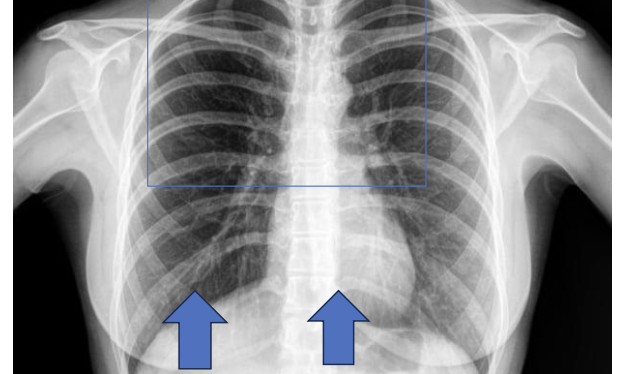

Identify the structure ? View?

Postero-Anterior, Chest